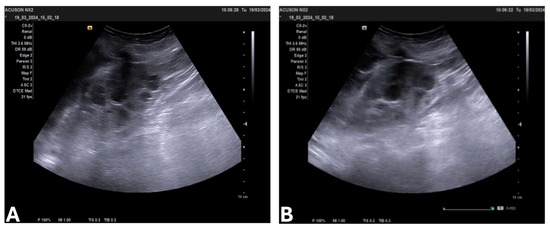

3.4. Laboratory Findings, Imaging, and Stage of ADPKD